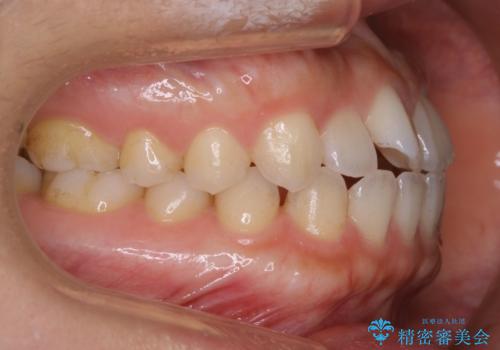

すきっ歯と噛み合わせの治療をしたいとのことで、インビザラインを用いて矯正治療を行うこととなりました。

すきっ歯の場合、ガタつきを治したりするのに必要なスペースが最初から空いているため、そのスペースを利用して比較的短期間で効率よく治療を進めることが可能となります。

噛み合わせの治療

初診時の写真では一見噛み合わせには問題がないように見えても、実際に精密な検査を行うと改善すべき点が見つかる場合も多くあります。